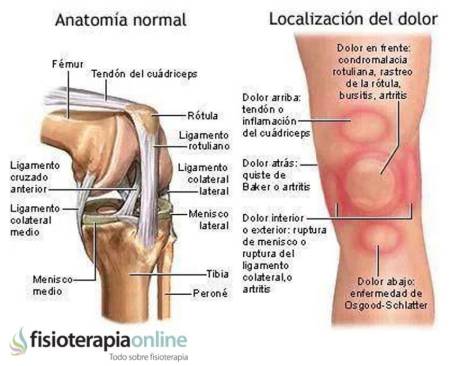

El síntoma más característico de la tendinitis de la pata de ganso es el dolor. A veces dolor constante, incluso nocturno (en fases agudas) y siempre se presenta dolor intenso al palpar la zona interna de la rodilla que puede apreciarse tumefacta.

Coma toda tendinitis, en su fase inicial puede doler únicamente al iniciarse el movimiento, correr, agacharse, para mejorar incluso desaparecer con el calentamiento, pero el dolor vuelve a aumentar después del ejercicio.

Si se agrava puede impedir el ejercicio, incluso dificultar la deambulación.

¿Sabes reconocer el dolor de rodilla? Infografía: los patrones del dolor de rodilla o gonalgia y las lesiones más comunes: